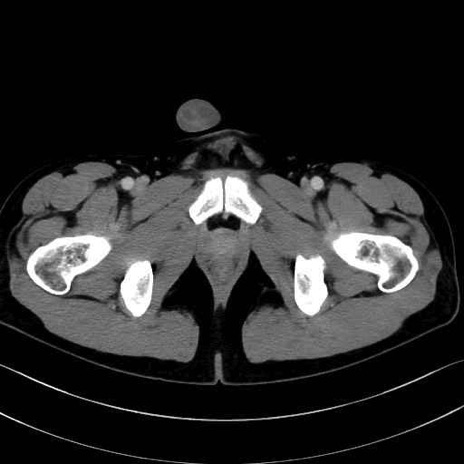

小殿筋 (Gluteus minimus)